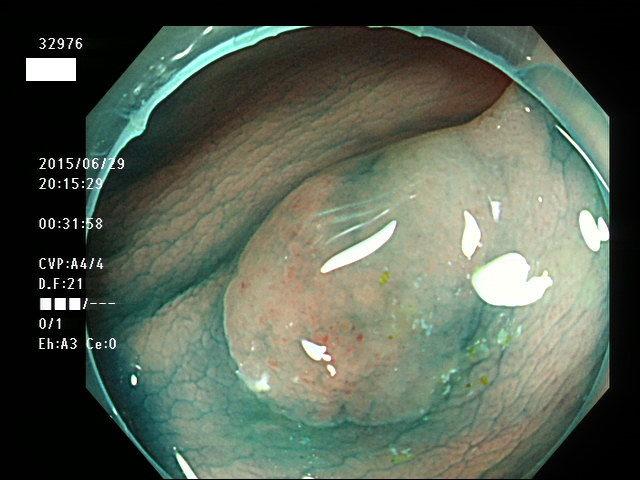

上記100名より抽出した平坦・陥凹型腺腫(=癌化の危険が高いが見落としやすい病変)の内視鏡写真

32901 32902 32903 32904 32905 32906 32907 32910 32911 32912 32915 32916 32918 32919 32920 32921 32922 32923 32924 32925 32926 32927 32928 32929 32931 32933 32935 32939 32941 32951 32953 32956 32957 32959 32961 32963 32964 32965 32967 32968 32971 32972 32973 32976 32978 32980 32981 32982 32986 32988 32989 32990 32994 32995 32998・・・・・・の55名